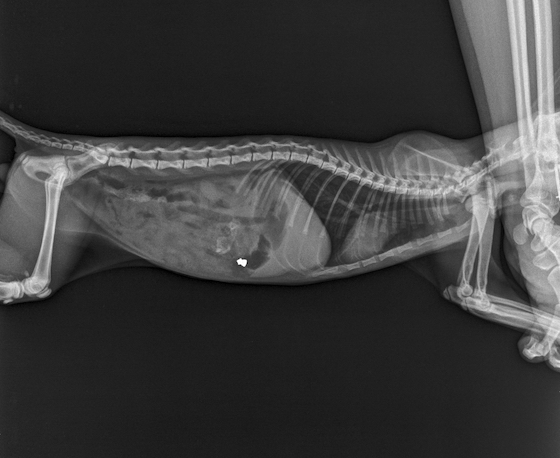

Η ακτινογραφία έκρυβε μια πολύ δυσάρεστη έκπληξη: Βλήμα από όπλο!

Πυροβόλησαν και σκότωσαν γατάκι στην Αλεξανδρούπολη!

Αποτροπιασμό προκαλεί το νέο περιστατικό κακοποίησης ζώου στην Άνθεια Αλεξανδρούπολης που αφορά σε ένα μικρό γατάκι που βρέθηκε πυροβολημένο.

Την απάνθρωπη αυτή είδηση έκανε γνωστή πριν λίγες ώρες το Καταφύγιο Αδέσποτων Ζώων Συντροφιάς Δήμου Αλεξανδρούπολης, μέσω ανάρτησης στο Facebook, σύμφωνα με την οποία το γατάκι βρέθηκε χτυπημένο σε κεντρικό σημείο της πόλης.

Το άτυχο ζώο παρά το γεγονός ότι μεταφέρθηκε σε κτηνίατρο κατέληξε.Την υπόθεση θα ερευνήσει η Αστυνομική Διεύθυνση Αλεξανδρούπολη μετά την καταγγελία που υπέβαλαν οι υπεύθυνοι του Καταφυγίου.

Τραγικό; Άθλιο; Συγκλονιστικό; Αποτρόπαιο; Οι λέξεις έχουν χάσει πλέον τη σημασία τους. Νεαρό γατάκι, εντός της Αλεξανδρούπολης, προσκομίστηκε στο κτηνιατρείο επειδή τις τελευταίες μέρες δεν είχε διάθεση για φαγητό και ήταν υποτονικό. Η ακτινογραφία έκρυβε μια πολύ δυσάρεστη έκπληξη: Βλήμα από όπλο! Δυστυχώς, το μπιζουδάκι κατέληξε.

Αύριο θα γίνει νεκροψία - νεκροτομή και καταγγελία στο ΑΤ Αλεξανδρούπολης για τα περαιτέρω.